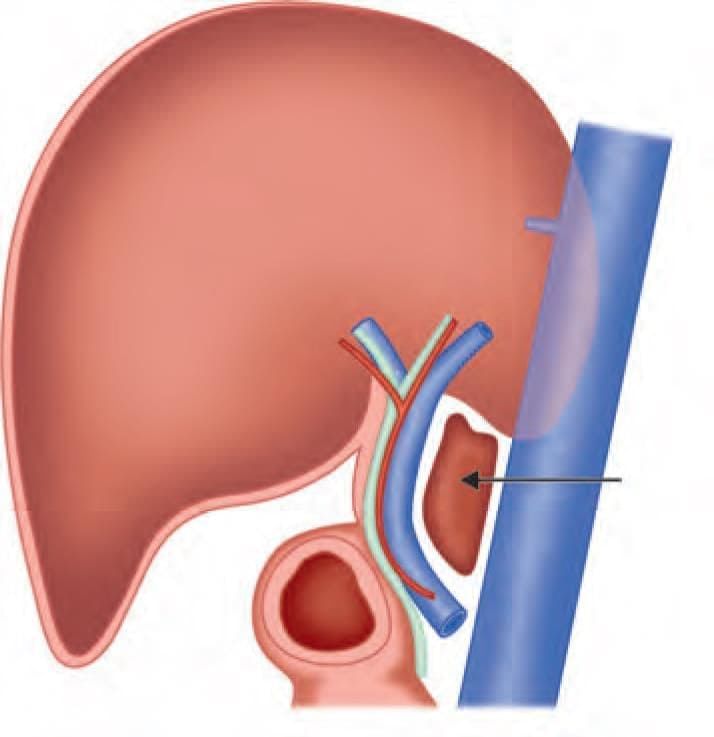

The anatomical structure at the arrow marked location is a defect in: (NEET-PG 2023)

Superior boundary of the arrow marked structure is: (INI-CET July 2021)